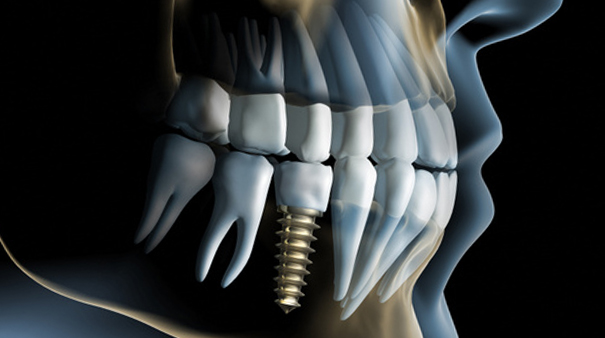

Come evitare il ponte tradizionale: l’Implantologia Stand Alone

Novembre 12, 2021

Sapevi che la tecnologia stand alone, tra le tecniche più avanzate di implantologia dentale, permette di recuperare un’efficiente masticazione e ritrovare la salute del dente senza limare i denti sani…

Cos’è l’implantologia zigomatica? Denti fissi con poco osso

Ottobre 27, 2021

Hai fatica nella masticazione, ti mancano molti dei tuoi denti naturali o ti mancano completamente, e il non poter perfettamente masticare e mangiare ti crea un certo disagio anche con…